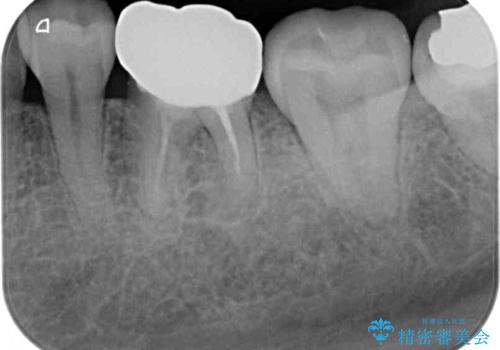

- 口を開けたときに目立ってしまう銀歯をセラミックに替えたいとのことで来院された患者様です。

上顎や親知らずにも銀歯がありましたが、今回の治療では目立つ下顎の銀歯4歯をセラミッククラウンやセラミックインレーに置き換えることにしました。